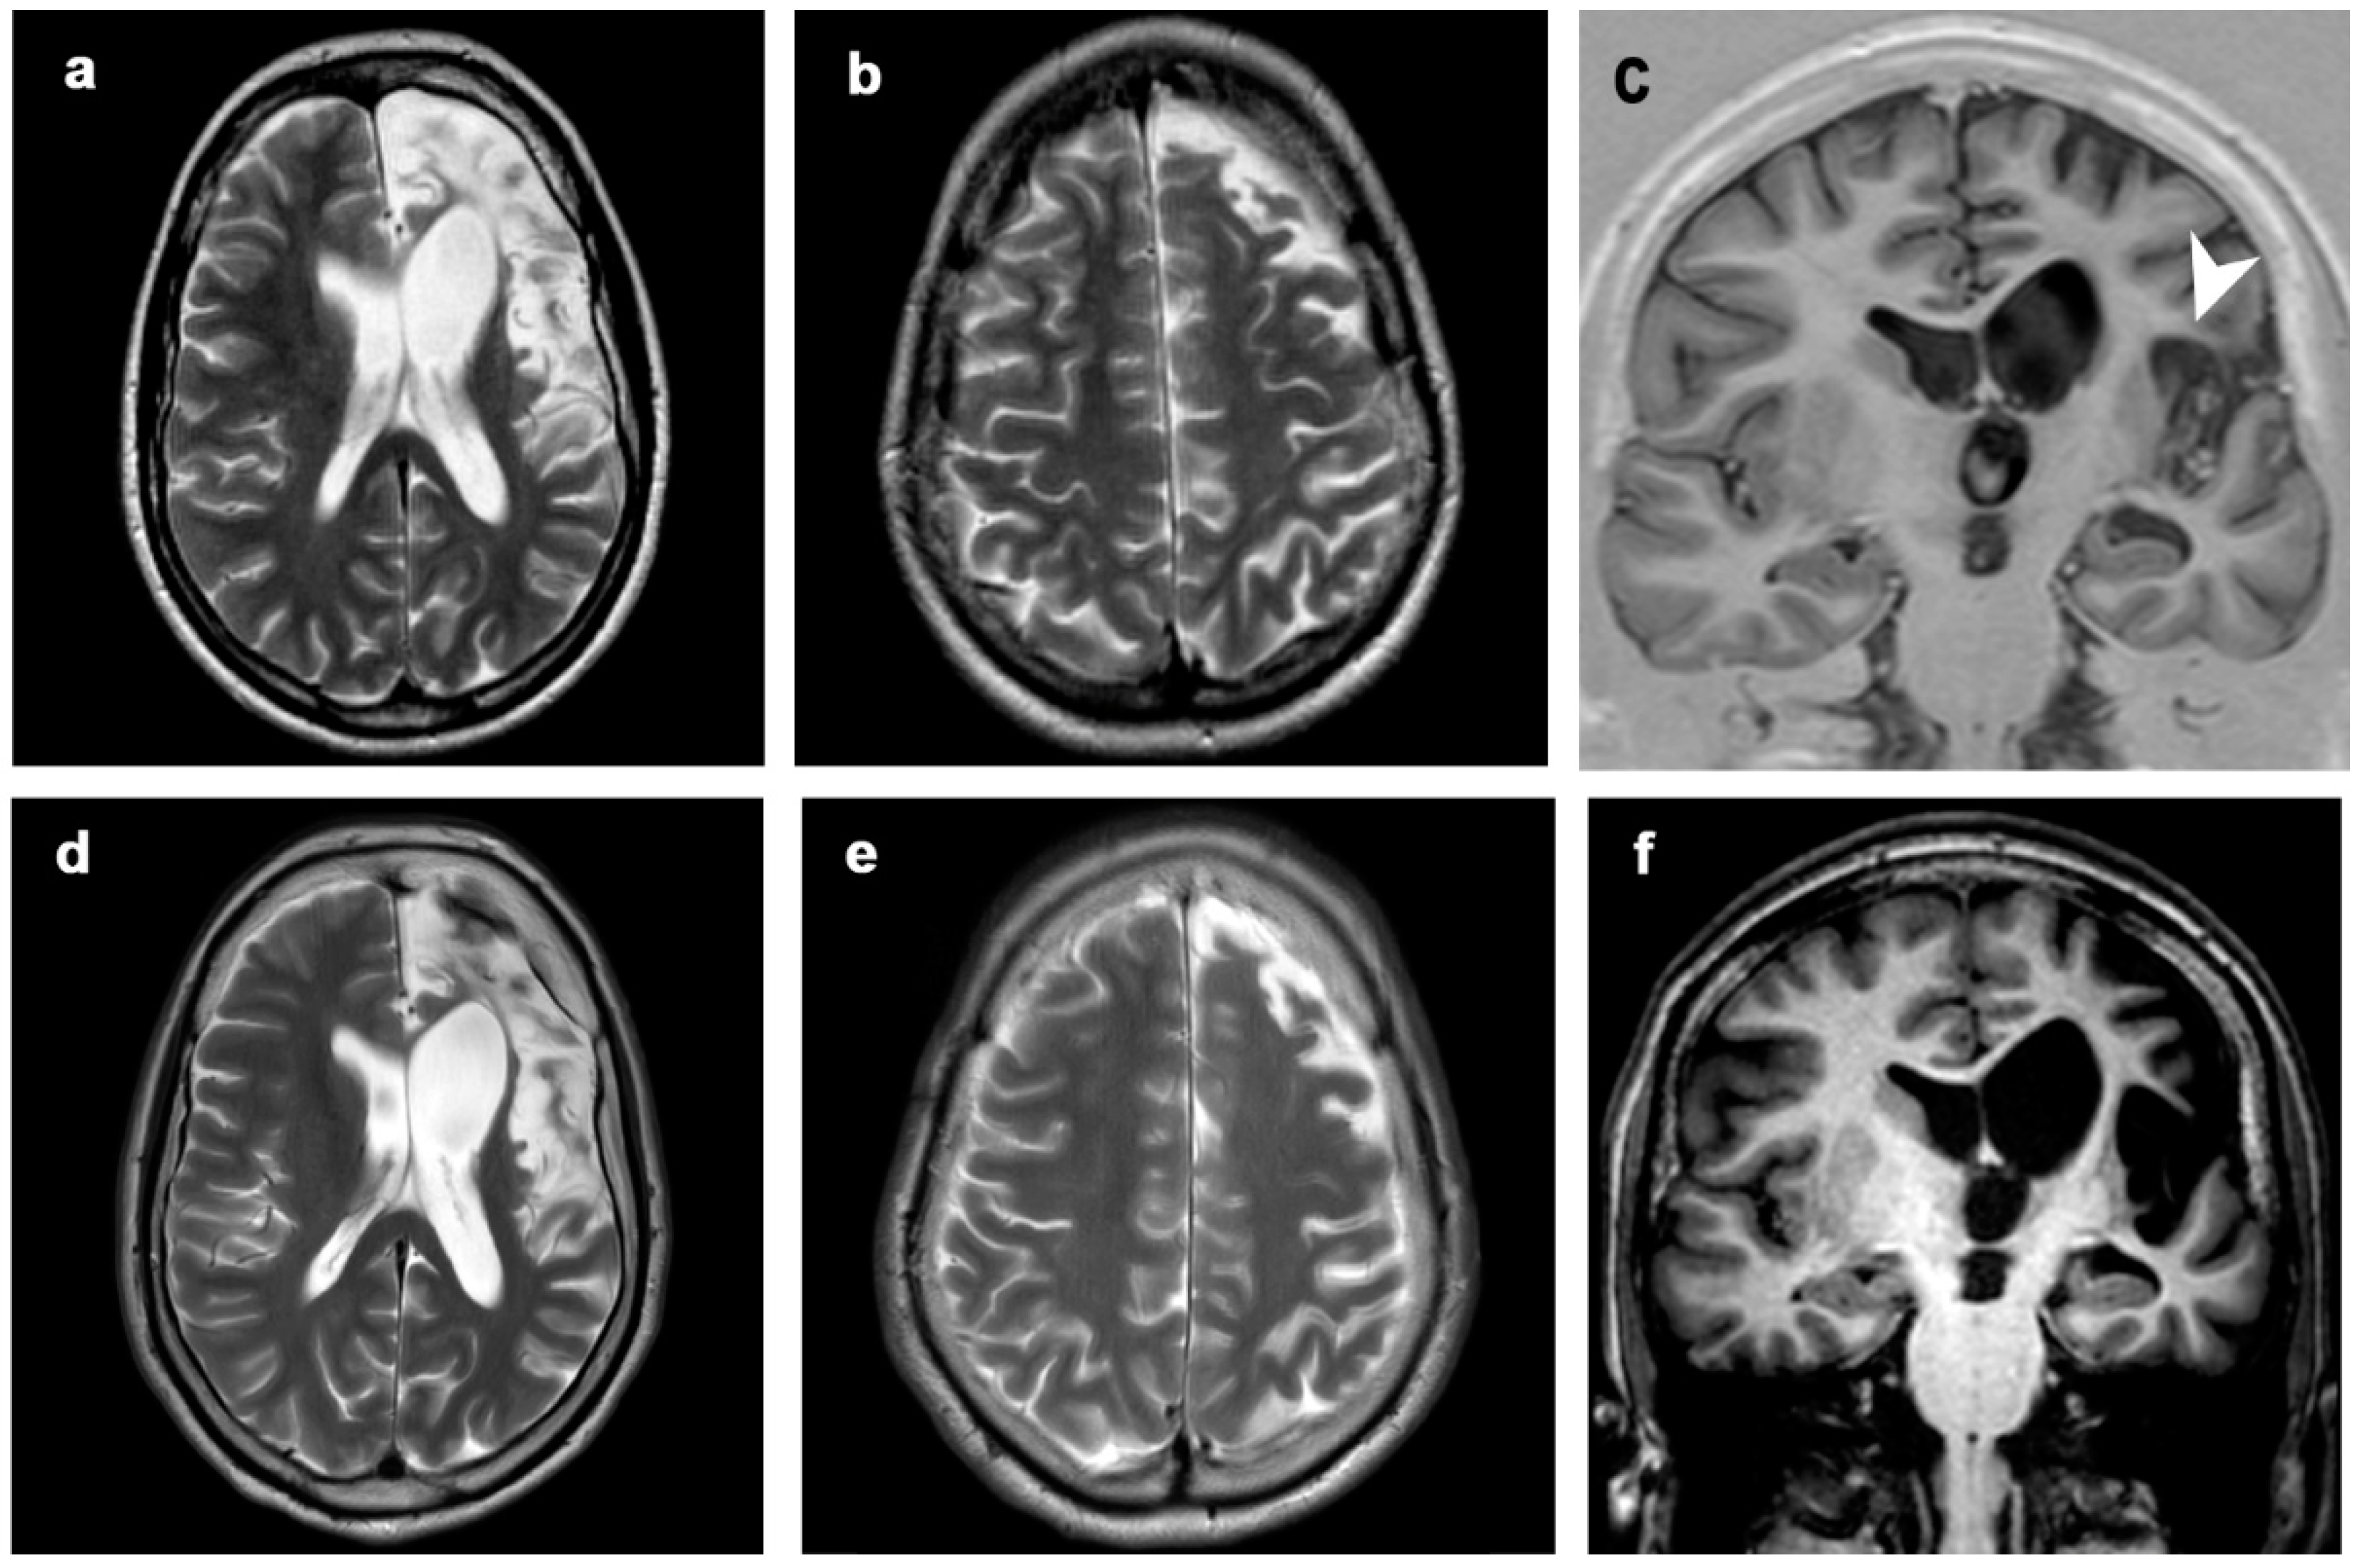

3.1. Atrophic Changes

3.2. Changes in Signal Intensity